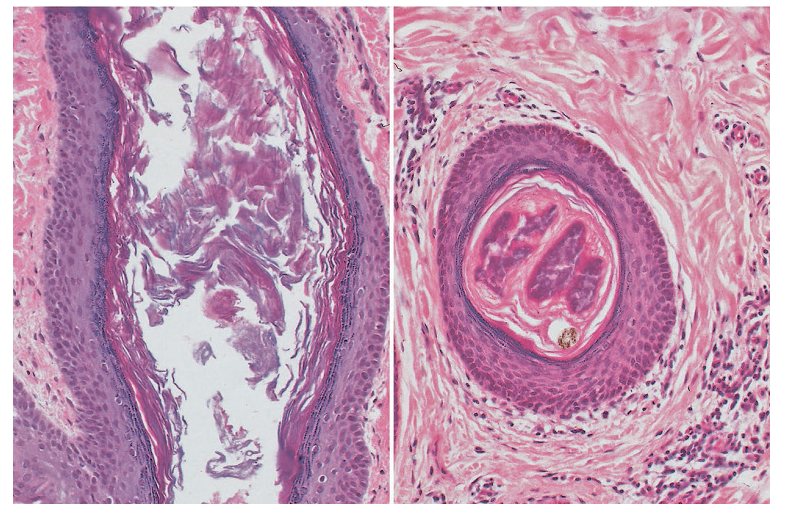

脂质微丝与微粉刺

前面已经介绍过脂质微丝(毛囊微丝)。这里大家可以在微观下,看看脂质微丝长什么样!

毛囊微丝(脂质微丝、毛囊管形)是生理性成分(油性皮肤大部分都会有脂质微丝),并不是痤疮表现的一部分,而微粉刺代表痤疮的早期皮损。从上图可以看出,毛囊导管无明显扩张,脂质粉丝呈细长样,微丝内含有细菌菌落。

微粉刺的横截面病理图

微粉刺虽然是痤疮的早期皮损,但也是肉眼无法看到的。图中可以看到,毛囊导管扩张,毛囊上皮可见颗粒层,并包裹着角化细胞微丝。腔内充满痤疮丙酸杆菌。

左图:微粉刺,右图:2条脂质微丝